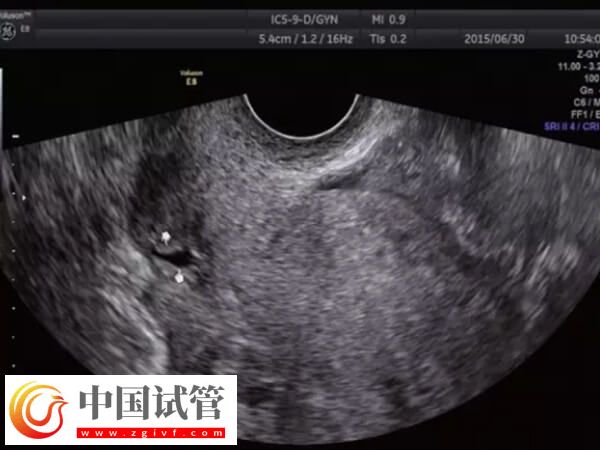

子宫憩室一般也叫剖宫产切口憩室或者子宫切口瘢痕缺损,主要是因为剖宫产手术遗留的刀口组织恢复不佳,从而造成的一个子宫凹陷空间。女性出现子宫憩室时,通过试管婴儿技术助孕怎么样,可以参考下列内容:

不过因个体之间存在较大的差异,所以子宫憩室能否做试管婴儿,还需要根据患者的年龄、症状、既往妊娠并发症、子宫腔的状态、憩室的大小、疤痕处的肌层厚度等多方面进行判断,患者可以直接前往医院咨询相关医生即可。